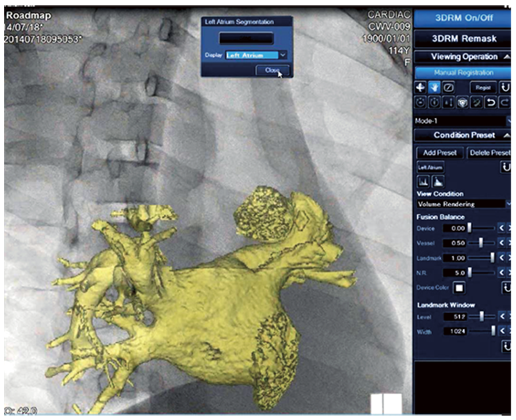

Функція автоматичної сегментації лівого передсердя (LA)

Об’ємні дані, отримані на КТ або МРТ, можуть бути імпортовані на робочу станцію ангіографа, автоматично сегментовані для перегляду лівого передсердя. Потім сегментоване зображення (LA) накладається на живе флюорографічне зображення і вручну коригується на поточній флюорографії. Об’єднане зображення є накладанням 3D-виду судинної анатомії та 2D-зображення ангіо, на якому візуалізується катетер. При обертанні С-дуги також обертається напівпрозоре об’ємне зображення.

Знімок екрана автоматичної сегментації LA на AWS